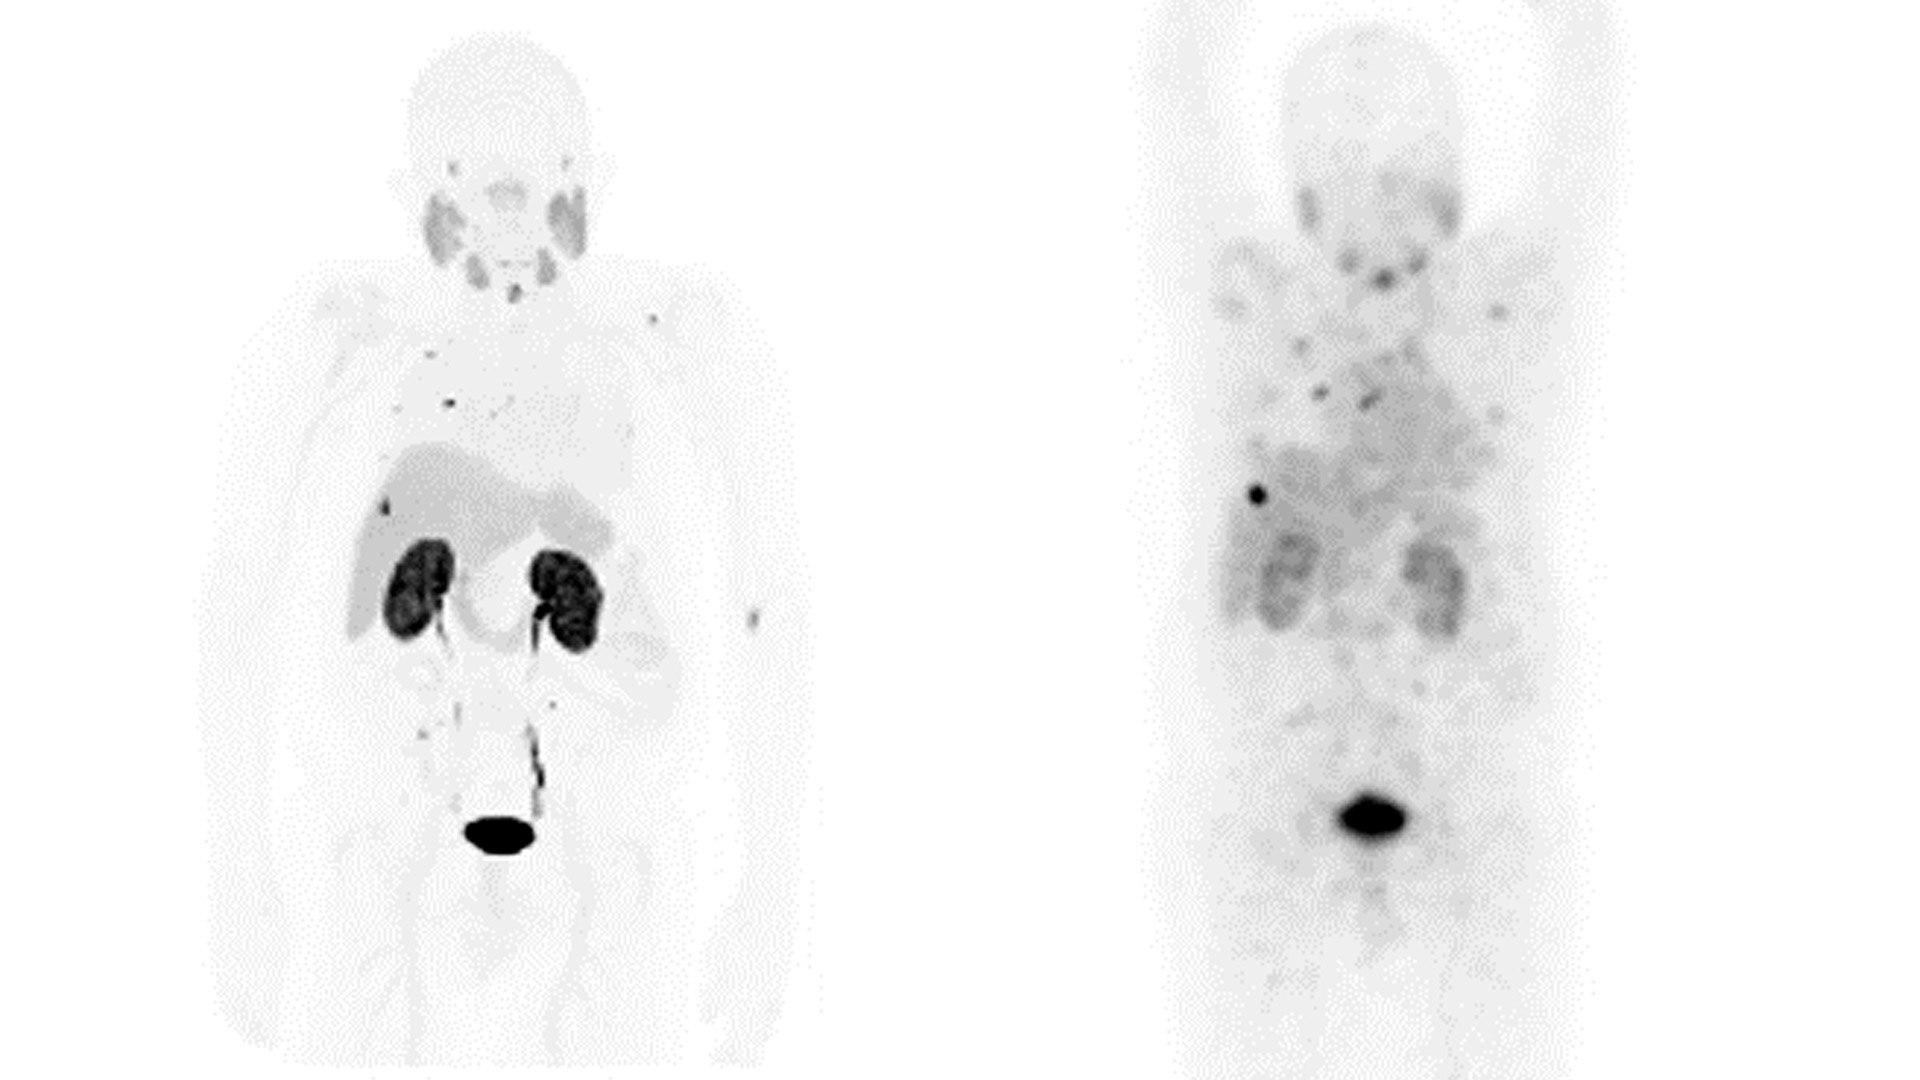

がんはそれぞれが固有のなものであり。その治療も個々によって異なります。GE HealthCareのTheranostics対応ソリューションは、がん治療における新時代に向けて特別に設計されています。がんの発見、診断、治療へのアプローチを変革するこの旅にご参加ください。医療の未来はここにあり、それはパーソナライズされたものへと進化していきます。

Theranosticsの患者ケア・パスウェイにおけるソリューションを提供することは患者予後を改善する大きな可能性を秘めています。

がん治療の未来-Theranostics

診断

GE HealthCareは、圧倒的な感度で診断の信頼性を向上させるソリューションを開拓しています。

Theranosticsを中心とする当社の画像診断ソリューションの専用ポートフォリオは、現在および将来の臨床医と患者のニーズを満たすように特別に設計されました。